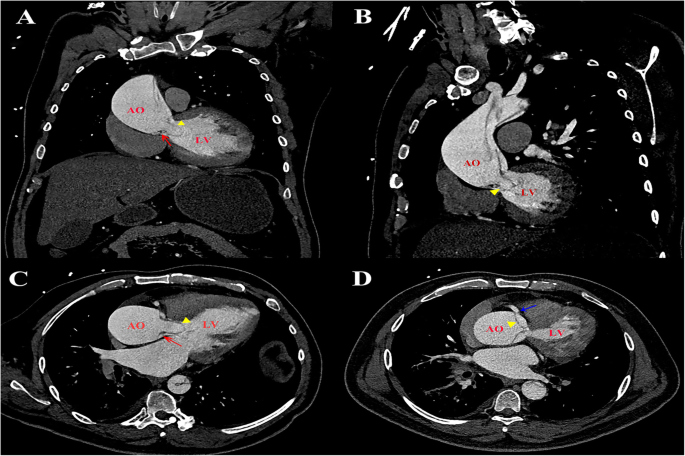

On this admission, the patient suffered from chest pain for about 1 h. The blood pressure was 143/42 mmHg, and there was no difference between two arms. He was conscious and neurological examination showed no abnormalities. Electrocardiography showed ST segment depression in leads I, aVL and V4–6, and preoperative hsTnT level was elevated to 45.60 ng/L (under 14 ng/L is normal). Contrast-enhanced computed tomography (CECT) revealed a Stanford type A aortic dissection with circumferential dissection of ascending aorta, and the proximal intimal flap prolapsed into the left ventricle outflow tract (LVOT) (Fig. 1). The coronary arteries arising from the true aortic lumen were not involved in the dissection. The dissection extended distally to brachiocephalic trunk, bilateral common carotid artery, and left subclavian artery, and ended at right common iliac artery. TTE indicated aortic dissection with a proximal intimal flap moving in and out of the LVOT in synchronicity with the cardiac cycle causing severe AR. He was therefore scheduled for urgent surgical treatment. Intraoperative TEE further confirmed a balloon-like intimal flap prolapsing into LVOT during diastole, which interfered with aortic valve cusp mobility, causing severe AR (Fig. 2, Supplementary material video 1–4). However, regurgitant flow was concentrated in a balloon-like intimal flap, concealing the degree of preexisting aortic insufficiency. The LV was dilated to 7.0 cm in diameter with mild left ventricular wall hypertrophy, and mild left ventricular lateral wall motion abnormalities. The ascending aorta was severely involved by dissection and therefore, cardiopulmonary bypass was instituted by cannulation of right atrium and right axillary artery combined with right femoral artery. Surgical inspection confirmed that the intima of the ascending aorta had been torn away through almost all of its circumference and the dissection extended proximally to below the level of coronary arteries. However, the coronary arteries and aortic valve annulus were not involved with dissection. The aortic valve commissures were intact, and the aortic valve leaflets were degenerated with mild thickening and without prolapse and deformity. Bentall procedure (aortic valve replacement with ascending aorta graft implantation) and Sun’s procedure (total arch replacement using tetrafurcate graft with stented elephant trunk implantation) were performed. During hypothermic circulatory arrest, nasoparyngeal temperature was 25 °C and antegrade cerebral perfusion by combining right axillary artery with left common carotid artery was selected for cerebral protection. The total cardiopulmonary bypass time was 244 min, aortic cross-clamping time was 138 min and circulatory arrest time was 17 min. The surgery was uneventful, and the patient was discharged on the 7th postoperative day after a smooth recovery. Histopathological analysis revealed myxoid degeneration of aortic valve and ascending aortic wall.

An intimal flap prolapsed into the left ventricular outflow tract in coronal view (A), sagittal view (B) and axial view (C and D) by CECT. Red arrow: aortic valve leaflet. Blue arrow: right coronary artery ostia. Yellow arrowhead: intimal flap. AO: aorta; LA: left atrium; LV: left ventricle; CECT: contrast-enhanced computed tomography